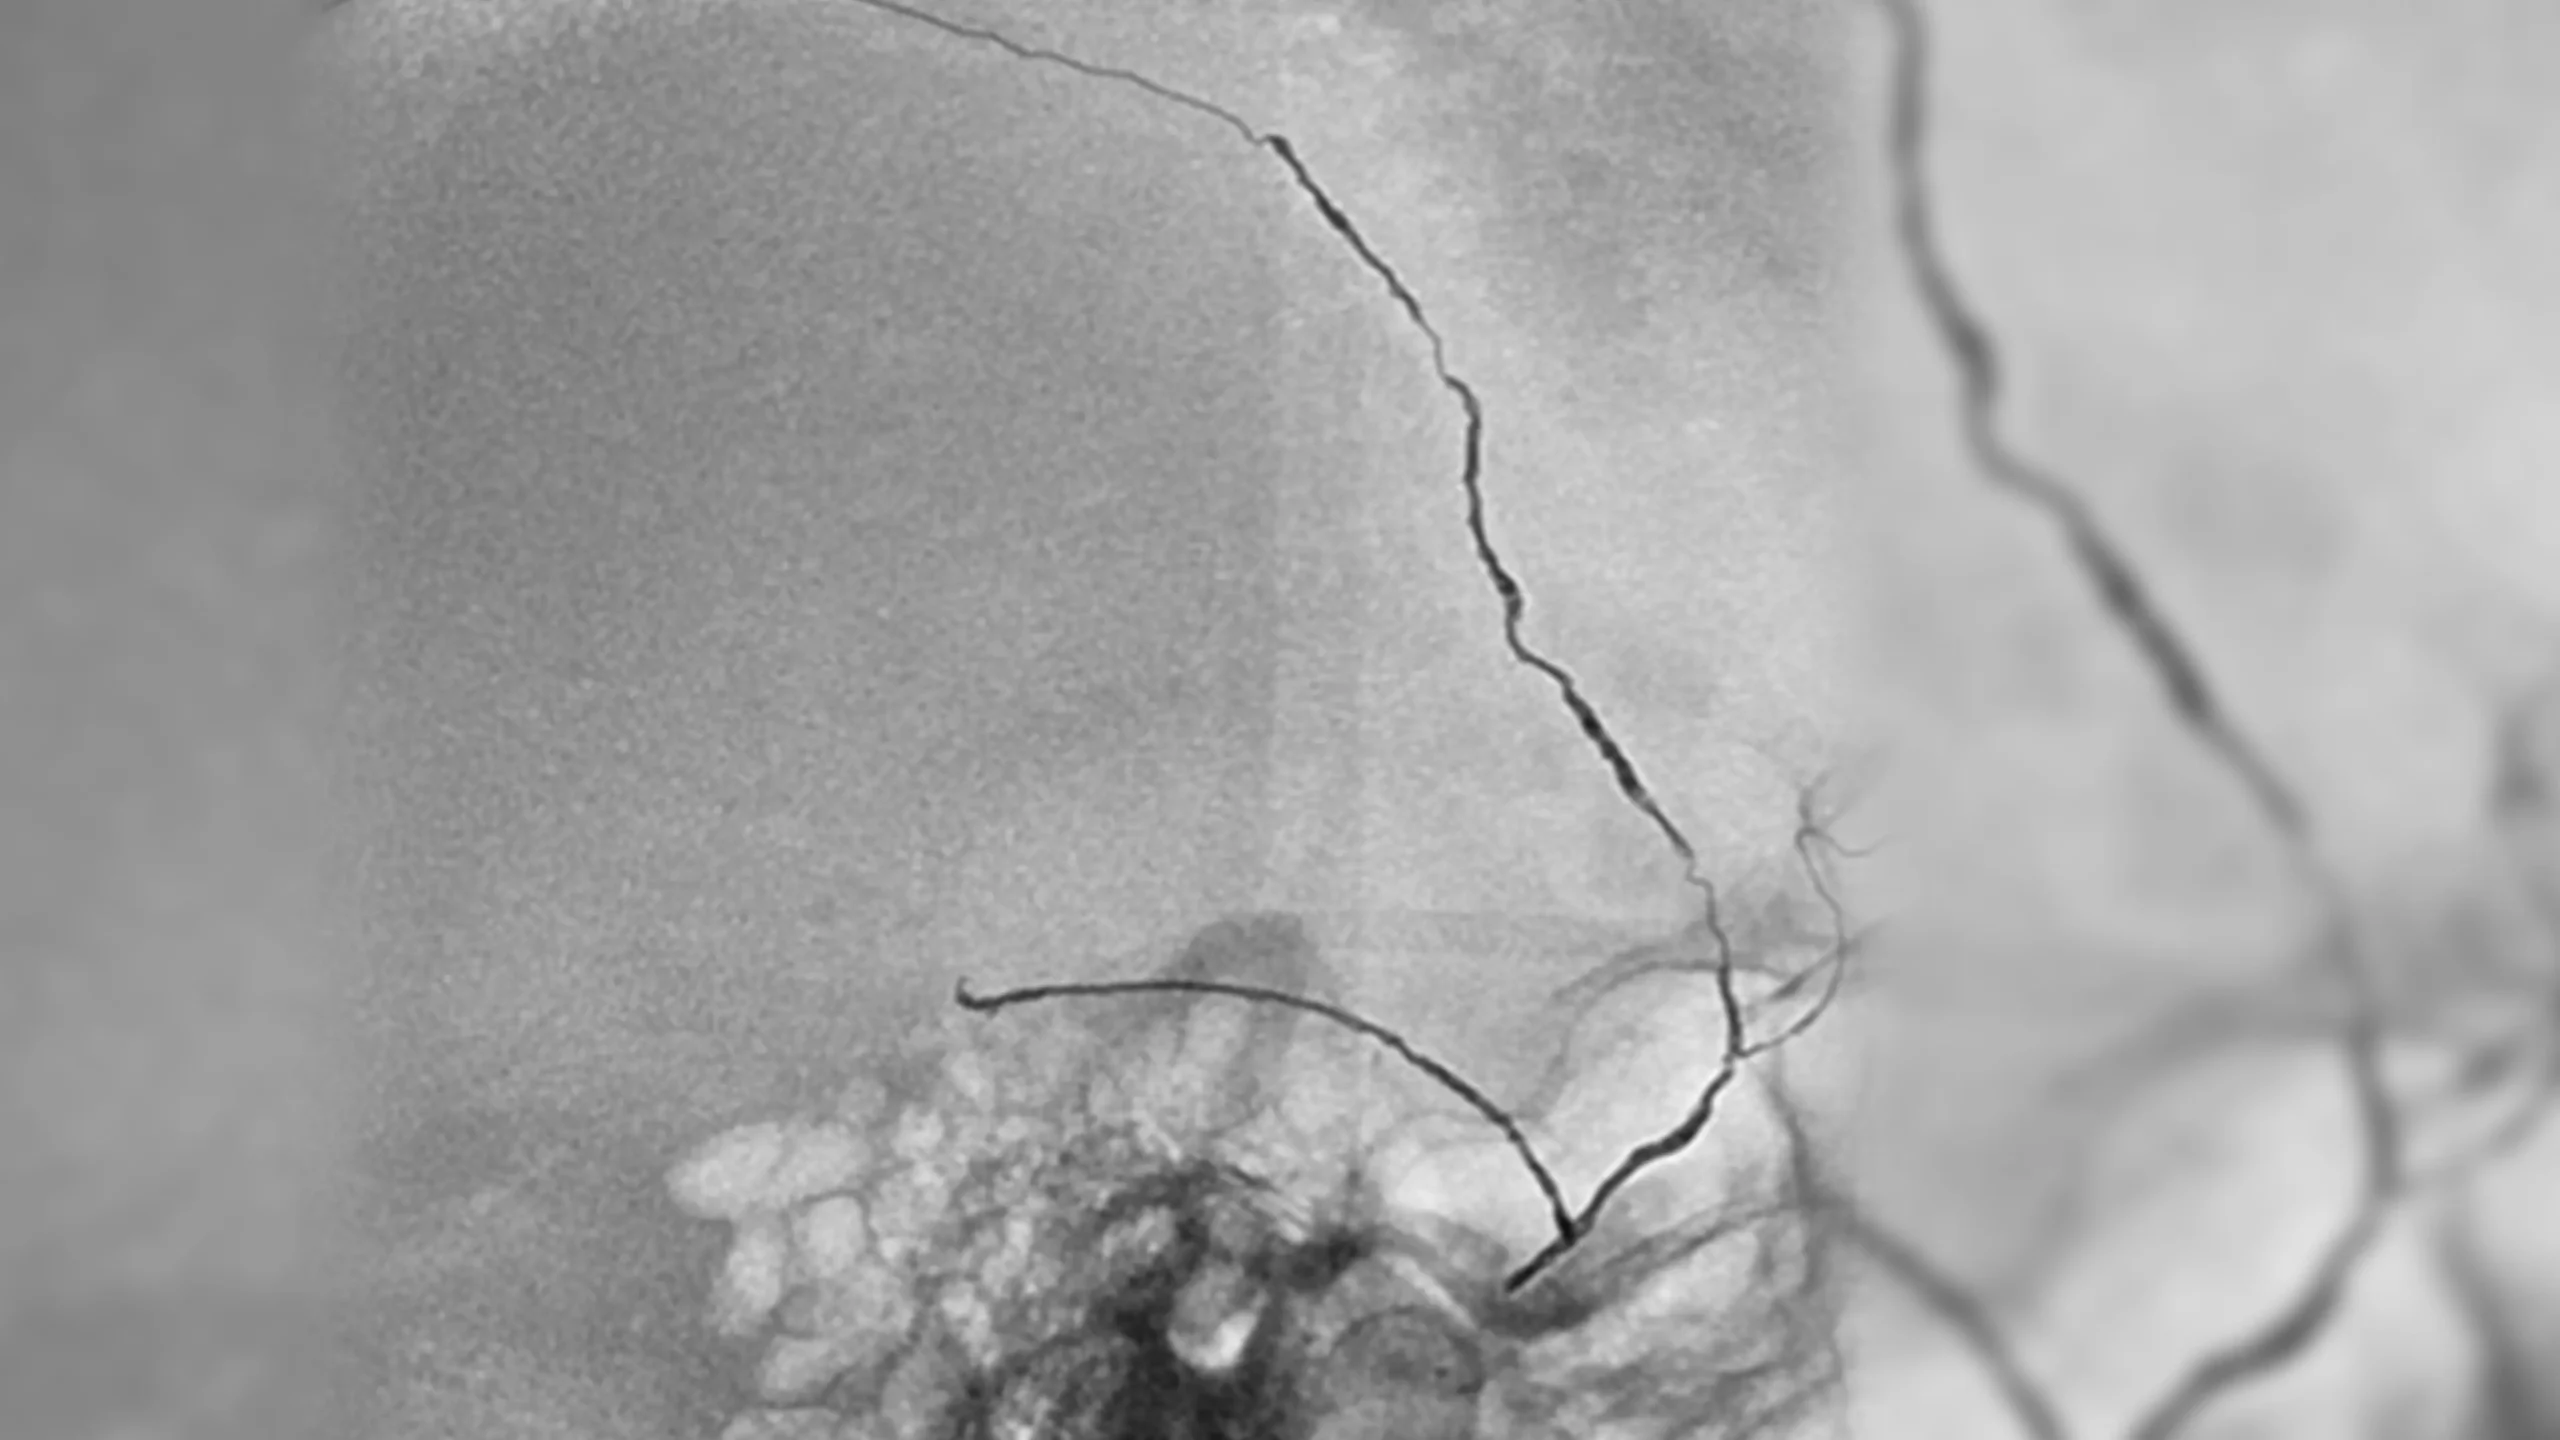

angiogram of an embolization coil place in an aneurysm

15 mm ICA terminus aneurysm coiled with PC400 and PAC400, 46% PD

Aneurysm

• PC400: optimized for aneurysm embolization

• Offered large volume with .020″ platform

• Supported by BENCHMARK family for stable access